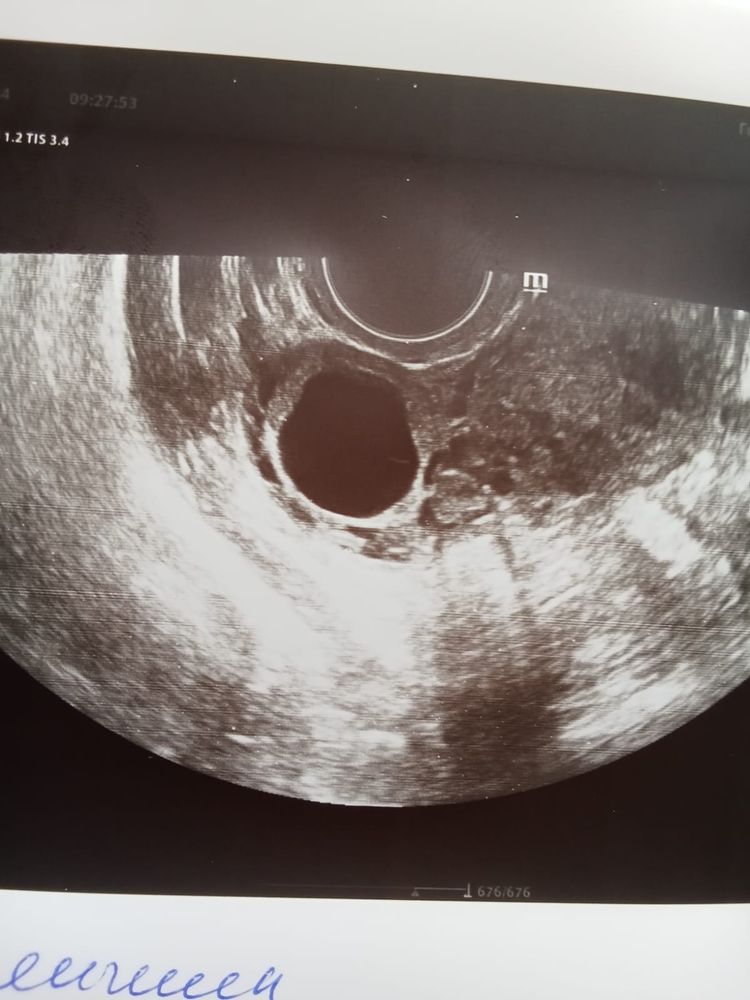

Была на узи на 22 дц, ДФ был 14 мм, эндометрий 1 см, на 25 дц тест на овуляций прям горел, потом через 3 дня начались прогестероновые выделения. Сегодня на 31 дц сходила на фолликулометрию, уже 5 дпо, жидкости нет, сказали, что теоретические ее уже может и не быть на 5 дпо, эндометрий 1 см, и под самый конец узи врач нашла типа дф 17 мм. Не понимаю как такие выделения если не было овуляции и как дф вырос только на 3 мм за 10 дней. Васкуляризацию не смотрела, и теперь сижу и гадаю могла ли она перепутать дф с жт? Поделитесь своими историями🙏❤️